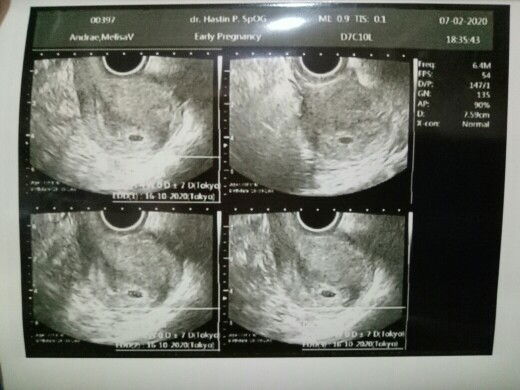

JK janin

Mitos bun, lebih baik usg aja bun biar tau pasti.

mitos bund, langsung usg aja biar jelas semuanya